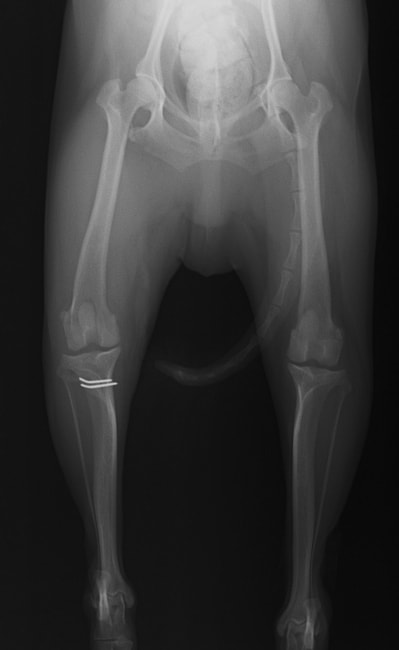

■ 症例20 ポメラニアン 8ヶ月 1.8kg

左右膝蓋骨脱臼 グレードⅢ

2ヶ月前から間欠的跛行が認められ、両膝の膝蓋骨脱臼整復術を行った。

手技は縫工筋及び内側広筋の解放、脛骨粗面の外側転位、滑車ブロック形造溝術、内外側関節包の縫縮を選択し実施した。

右側の膝蓋骨脱臼は上記手技で整復されたものの、左側はそれのみでは膝蓋骨が浮く様子が認められた。その為、PDS縫合糸にて膝蓋靱帯を1糸のみ縫合し、靱帯の縫縮を行った。

膝蓋骨脱臼は膝関節における膝蓋骨の内外側の脱臼と定義されるが、時として単純な内外の脱臼ではなく、膝蓋骨が大きく前方に浮き上がるように脱臼する場合がある。特にトイプードルやポメラニアンといった犬種に多く認められる。

内側脱臼に加えて前方への浮き上がりを矯正する為に、従来より脛骨粗面転移により膝蓋靭帯を外方と下方に引っ張り、固定する方法を選択する。膝蓋骨の前方への浮き上がりが軽度の場合は、従来法ではなく関節包の縫縮で対応していた。しかし、一部の症例で膝蓋骨の動きが悪くなり伸展機構が円滑に機能せずロボット様歩行になるケースがあった。

その為、膝蓋靭帯自体を縫縮する方法を採用した。この方法により、膝関節の伸展機構を妨げず膝蓋骨の軽度の浮きを矯正することが可能となった。

本症例の経過は良好である